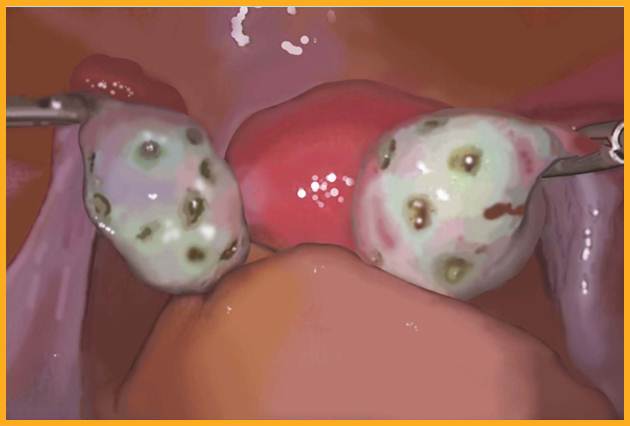

多囊卵巢综合征卵巢和正常卵巢示意图

1.卵巢变化 大体检查:双侧卵巢均匀性增大,为正常妇女的2~5倍,呈灰白色,包膜增厚、坚韧。切面见卵巢白膜均匀性增厚,较正常厚2~4倍,白膜下可见大小不等、≥12个囊性卵泡,直径在2~9mm。镜下见白膜增厚、硬化,皮质表层纤维化,细胞少,血管显著存在。白膜下见多个不成熟阶段呈囊性扩张的卵泡及闭锁卵泡,无成熟卵泡生成及排卵迹象。